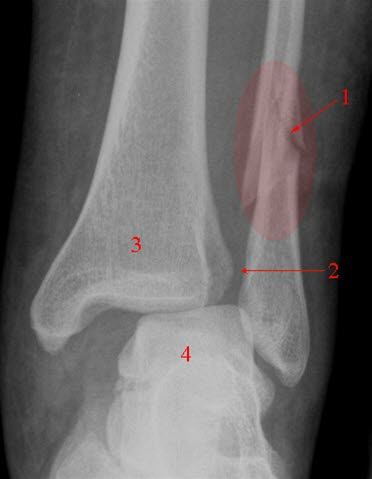

Ankelfraktur, ustabil

Brudd (1) gjennom distale fibula med ruptur av syndesmosen (2). Betydelig sprik i ankelgaffelen

- Brudd

- Syndesmose

- Tibia (skinnebenet)

- Talus